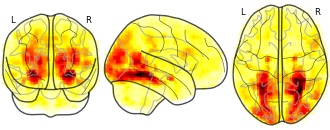

Citation: Hur, J., Kaplan, C. M., Smith, J. F., Bradford, D. E., Fox, A. S., Curtin, J. J., & Shackman, A. J. (in press). Acute alcohol administration dampens central extended amygdala reactivity. Scientific Reports.

Alcohol use is common, imposes a staggering burden on public health, and often resists treatment, underscoring the need to develop a deeper understanding of the underlying neurobiology. The central extended amygdala (EAc)—including the bed nucleus of the stria terminalis (BST) and the central nucleus of the amygdala (Ce)—plays a key role in prominent neuroscientific models of alcohol drinking, but the relevance of these regions to acute alcohol consumption in humans remains unknown. Using a single-blind, randomized-groups design, multiband fMRI data were acquired from 49 social drinkers while they performed a well-established emotional faces paradigm after consuming alcohol or placebo. Relative to placebo, alcohol significantly dampened reactivity to emotional faces in the BST. To rigorously assess potential regional differences in activation, data were extracted from unbiased, anatomically predefined regions-of-interest. Analyses revealed similar levels of dampening in the BST and Ce. In short, alcohol transiently reduces reactivity to emotional faces and it does so similarly across the two major divisions of the human EAc. These observations reinforce the translational relevance of addiction models derived from preclinical work in rodents and provide insights into the neural systems most relevant to the consumption of alcohol and the initial development of alcohol abuse in humans.Subject species

homo sapiens

Modality

fMRI-BOLD

Analysis level

group

Cognitive paradigm (task)

emotion processing fMRI task paradigm

Map type

T

- a